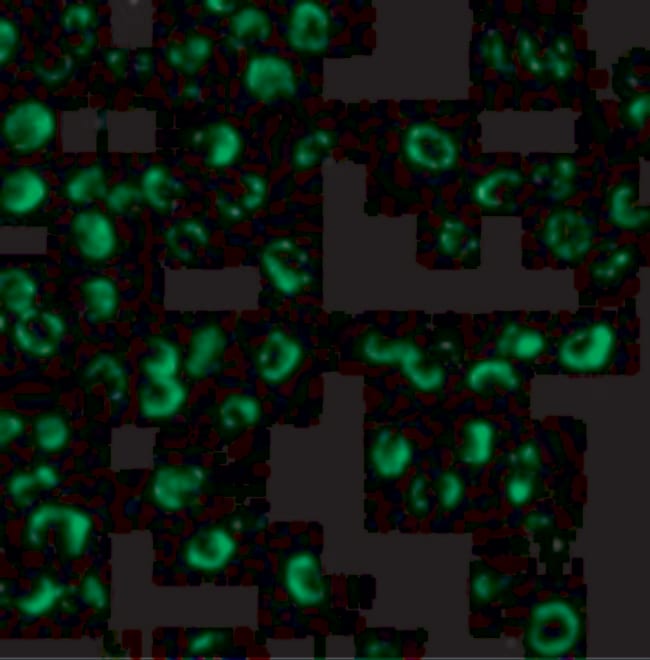

| Applications | Immunoprecipitation, Western Blot, Immunocytochemistry |